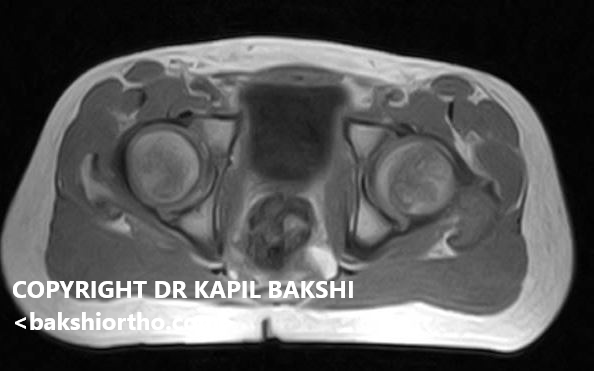

Previous Image Perthes medial flattening Shahzaib. 1.JPG MRI shows not all frames are involved Like Loading...